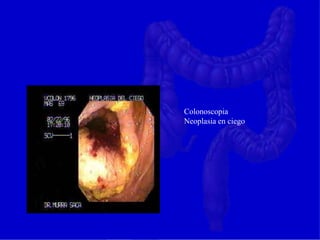

Colonoscopia

Neoplasia en ciego